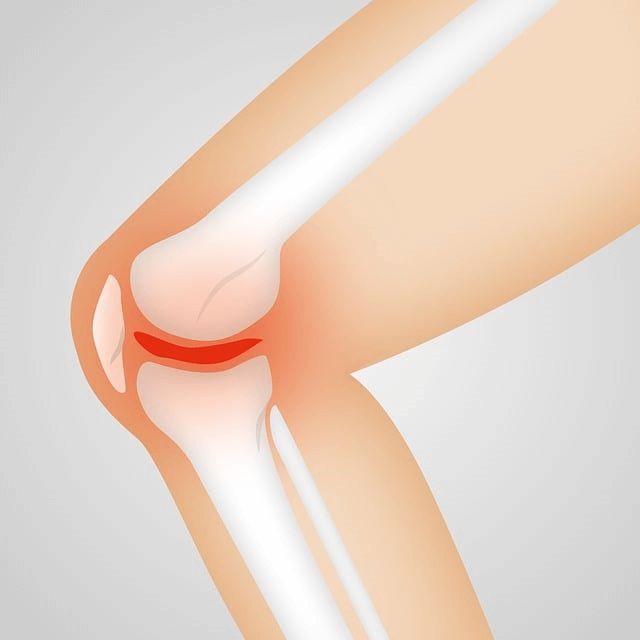

연골은 뼈와 뼈 사이에서 충격을 흡수하고 관절의 움직임을 부드럽게 하는 조직인데요.

콘드로이친은 이 연골의 수분을 유지하고 탄력을 제공하는 데 중요한 역할을 합니다.

콘드로이친은 관절염, 특히 골관절염의 증상을 완화하는 데 도움을 줄 수 있다고 알려져 있습니다.